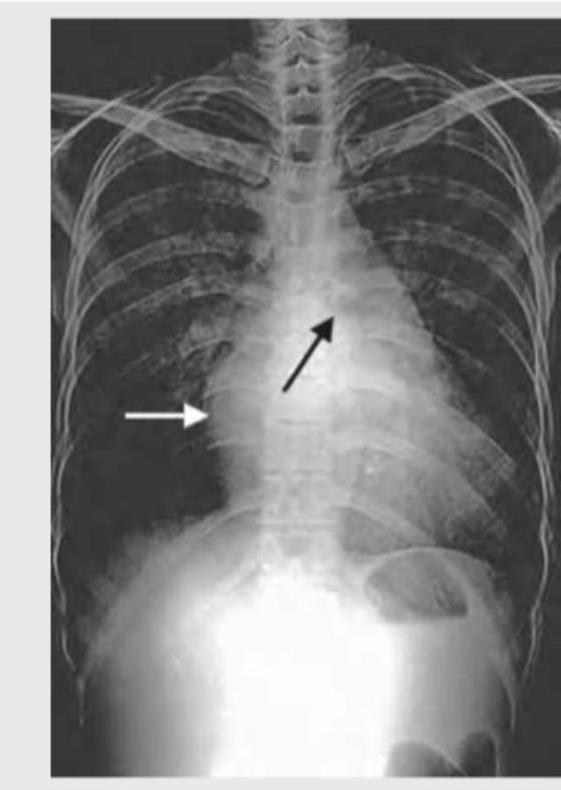

CXR was done for a 15-year-old boy with low cardiac output. Which is incorrect about the patient?

Explanation: ***Carey Coombs murmur*** - A **Carey Coombs murmur** is a mid-diastolic murmur typically heard in **acute rheumatic fever** due to active mitral valvulitis, which causes relative mitral stenosis. - The patient's CXR indicates **Coarctation of Aorta**, as evidenced by the **reverse 3 sign** (figure-of-3 sign) and **rib notching** from collateral circulation. - Carey Coombs murmur is **not associated with coarctation of aorta**, making this the **incorrect finding** for this patient. *Reverse split S2* - A **reverse split S2** (paradoxical splitting) occurs when the **aortic component (A2) follows the pulmonary component (P2)** due to delayed left ventricular ejection. - This can occur in conditions causing **left ventricular outflow obstruction** such as severe aortic stenosis or coarctation of aorta. - In coarctation, increased LV afterload can delay aortic valve closure, potentially causing reverse splitting of S2. *Straightening of left heart border* - **Straightening of the left heart border** on CXR is observed in conditions causing **left ventricular hypertrophy** or prominence of the pulmonary artery. - In coarctation of the aorta, the left ventricle works against increased afterload, leading to **concentric LV hypertrophy**, which can result in this CXR finding. *Ejection systolic murmur* - An **ejection systolic murmur** is commonly heard in coarctation of aorta due to turbulent flow across the narrowed segment. - The murmur is best heard over the **left infraclavicular area and back** (between the scapulae). - Associated aortic stenosis or bicuspid aortic valve (present in 50-85% of coarctation cases) can also produce an ejection systolic murmur at the aortic area.